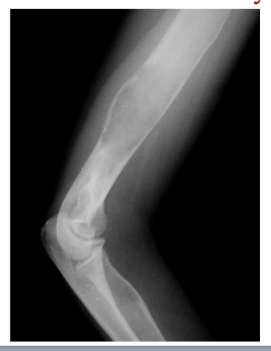

Ostoid osteoma

What is this?

Cells within an osteoid osteoma or osteoblastoma (hard to tell apart)

New bone cells forming